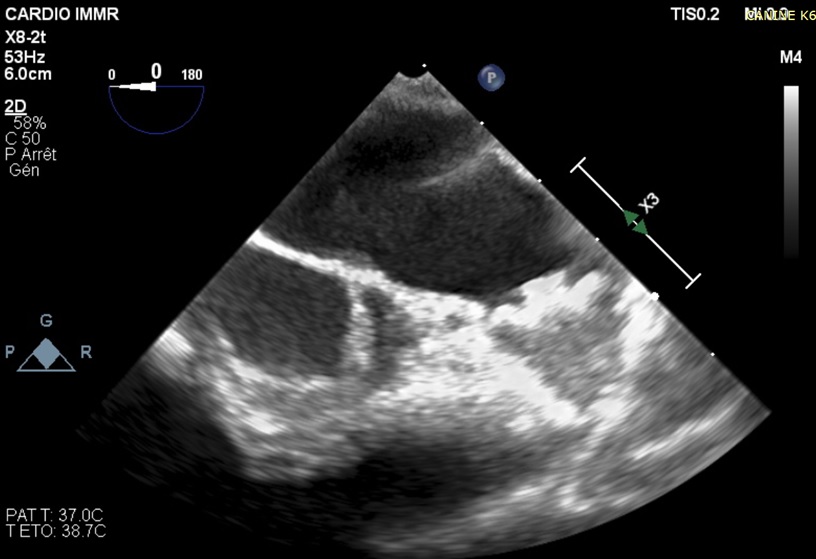

ECHO image of device implanted (pre-clinical)

ECHO image of device in pre-clinical